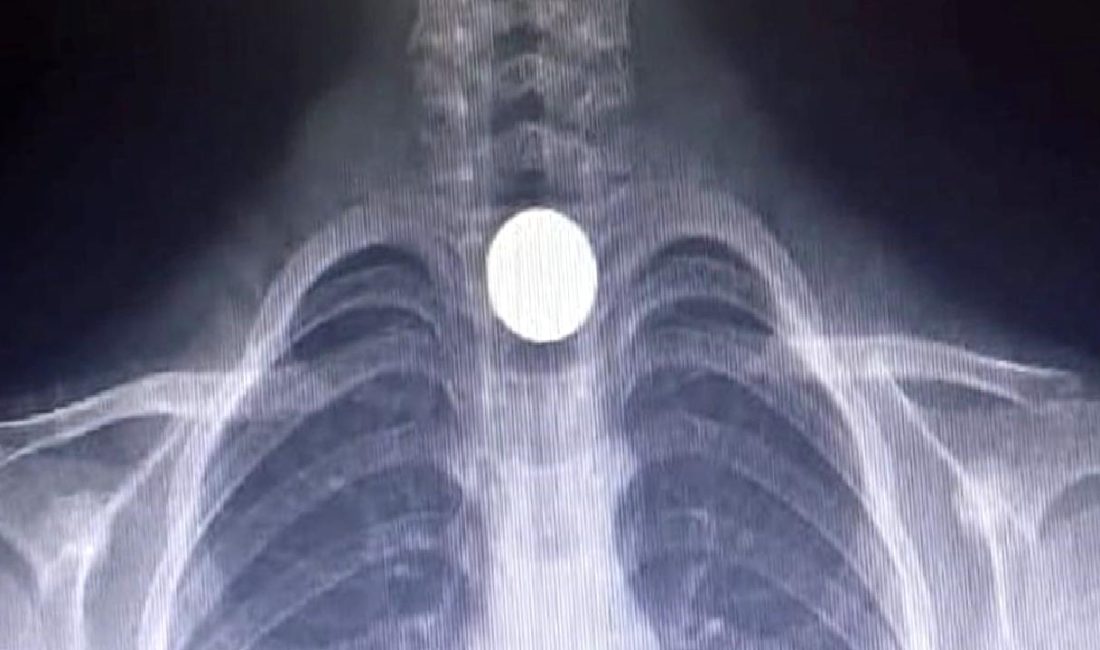

Hastanede yapılan detaylı tetkiklerde, Yusuf’un yemek borusuna 50 kuruşluk madeni para kaçtığı tespit edildi. Ailesi, bu duruma büyük bir üzüntü ve endişe ile karşılık verirken, hastane ekibi hızlı bir şekilde müdahale etmeye başladı.

Yusuf’un tedavisine devam edilmesi gerektiği anlaşılınca, ambulansla Bursa Yüksek İhtisas Eğitim ve Araştırma Hastanesi‘ne sevk edildi. Burada, uzman doktorlar tarafından gerçekleştirilen başarılı bir ameliyatla, Yusuf’un yemek borusundaki para çıkarıldı.